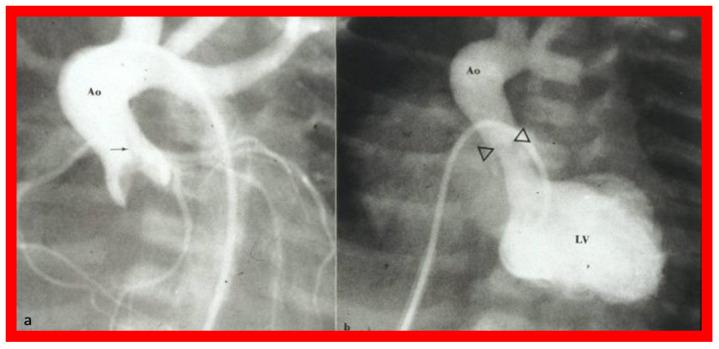

While investigating the outcomes of balloon dilatation procedures in patients with congenital obstructive lesions of the heart, several parallel observations were made. The purpose of this review is to present these observations/phenomena/innovations related to balloon dilatation of pulmonary stenosis (PS), aortic stenosis (AS), and aortic coarctation (AC). In subjects who had balloon pulmonary valvuloplasty (BPV), development of infundibular obstruction, electrocardiographic (ECG) changes, changes in right ventricular filling, role of balloon/annulus ratios on the results of BPV, and double balloon vs. single balloon BPV will be reviewed. In patients who had balloon aortic valvuloplasty (BAV), causes of aortic insufficiency and trans-umbilical venous approach for BAV are tackled. In children who had balloon angioplasty (BA) of AC, aortic remodeling and biophysical response after BA of AC are discussed.

在研究患有先天性心脏阻塞性病变患者的球囊扩张手术结果时,进行了几项平行观察。本综述的目的是介绍这些与肺动脉狭窄(PS)、主动脉狭窄(AS)和主动脉缩窄(AC)球囊扩张相关的观察结果/现象/创新。在接受球囊肺动脉瓣成形术(BPV)的受试者中,将对漏斗部梗阻的发展、心电图(ECG)变化、右心室充盈变化、球囊/瓣环比率对BPV结果的作用以及双球囊与单球囊BPV进行综述。在接受球囊主动脉瓣成形术(BAV)的患者中,探讨主动脉瓣关闭不全的原因以及BAV的经脐静脉途径。在接受AC球囊血管成形术(BA)的儿童中,讨论AC球囊血管成形术后的主动脉重塑和生物物理反应。